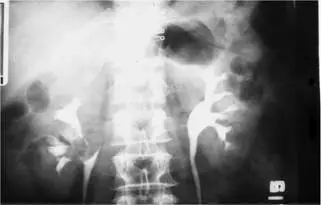

50歲男性病人主訴最近肉眼可見血尿。下圖為靜脈注射尿路X光攝影( intravenous urography )。最可能的診斷為何? 圖片描述

影像顯示雙腎輸尿道造影:

• 右側腎排泄對稱,腎盂及乳頭構造清晰,輪廓平滑。

• 左側腎乳頭及腎盂區域出現多發性、形狀不規則之放射透明充盈缺損,伴隨部分乳頭鈍化與乳頭截斷現象,顯示對比劑無法正常流入疑似侵犯區域。

此影像特徵符合上尿路尿路上皮性癌所致之輸尿管腔內生長與阻塞,腫瘤如乳頭狀或扁平增厚,黏附於尿路黏膜,造成腔內不規則充盈缺損與腎盂系統排泄障礙([emedicine.medscape.com](https://emedic